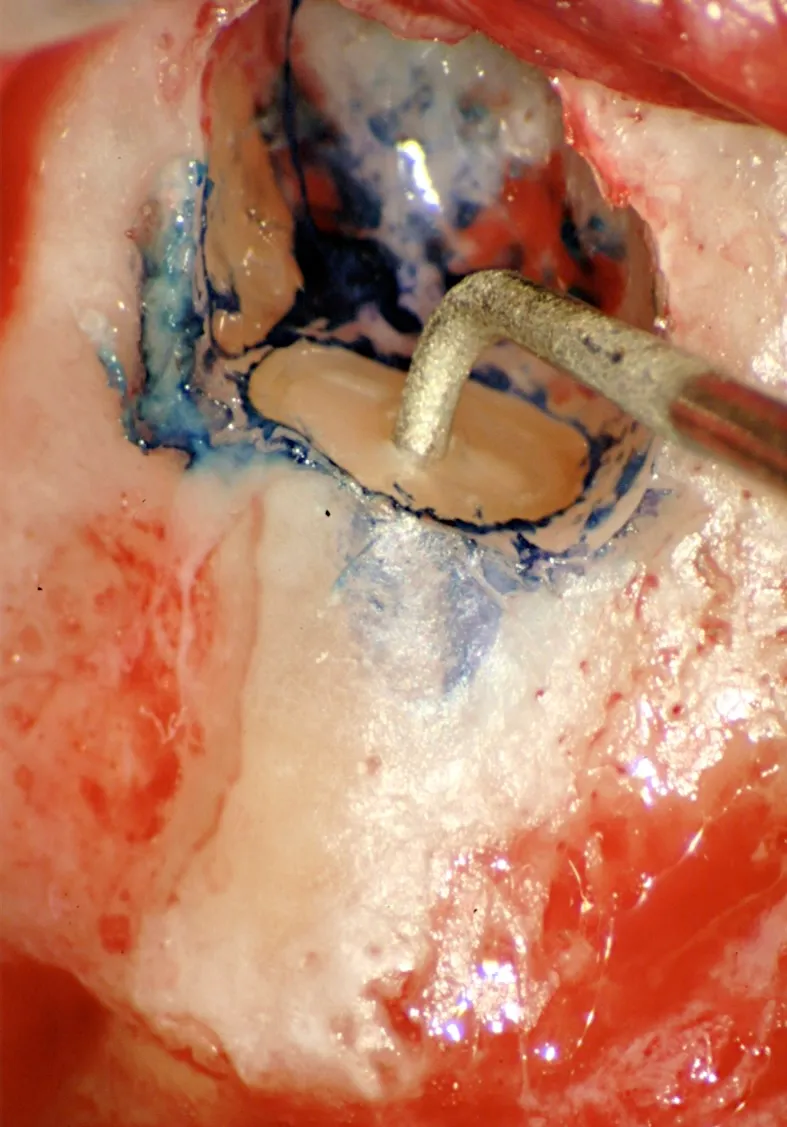

Microchirurgia Endodontica

Tecniche microchirurgiche per la risoluzione di casi complessi. Approccio chirurgico quando il trattamento ortogrado non è possibile.